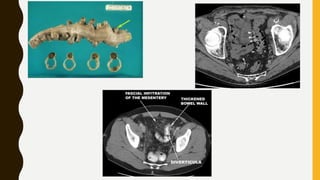

CT IN DIVERTICULITIS

• Typical CT appearance is of pericolic inflammatory change around

diverticulum, most commonly in sigmoid colon.

• Complications of diverticulitis include perforation, abscess

formation. CT is modality of choice to identify these and can be

used to guide percutaneous abscess drainage as a bridge to definite

surgery.

CT IN BOWEL WALL ISCHEMIA

• Iv contrast may be used to look for thrombus/emboli in mesenteric

vessel.

• Ischemia is difficult to diagnose radiologically, but may suspected

clinically- bowel wall thickening, submucosal edema, free fluid

(haemorrhagic) between the folds of mesentery. Ischemia is strongly

suspected if these findings are seen associated with loop obstruction

or strangulated herina

• Bowel wall ischemia leads to transmural infarction , evidence of

pneumatosis (air in bowel wall) . The air in bowel wall may track